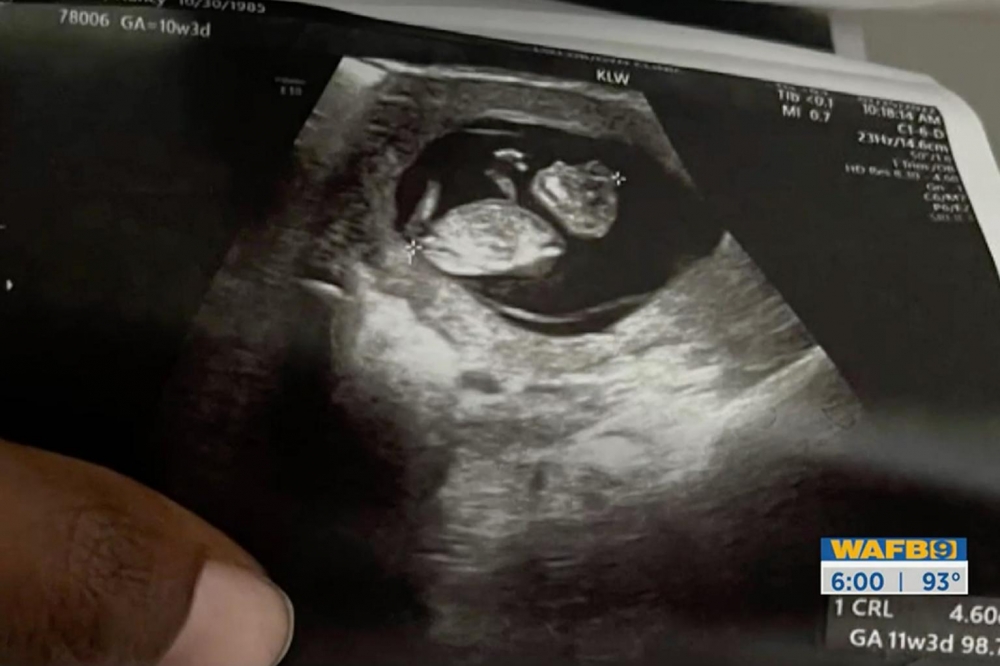

綜合外媒報道,來自美國路易斯安那州的36歲準媽媽Nancy日前召開記者發布會,申述墮胎禁令讓她面臨危險的情況。Nancy育有3名兒女,早前成功懷上第四胎,卻在第十週產檢時,被醫生告知胎兒罹患罕見先天性無腦異形(anencephaly),胎兒顱骨及腦袋將不會正常發育,導致胎兒胎死腹中,即使順利誕生也只能存活幾小時至幾天。Nancy憶述:「醫生告訴我,我的孩子出生後不久就會死亡,建議我終止妊娠,但他們礙於禁令,無法替我執行墮胎手術。」

Photo from 翻攝自WAFB